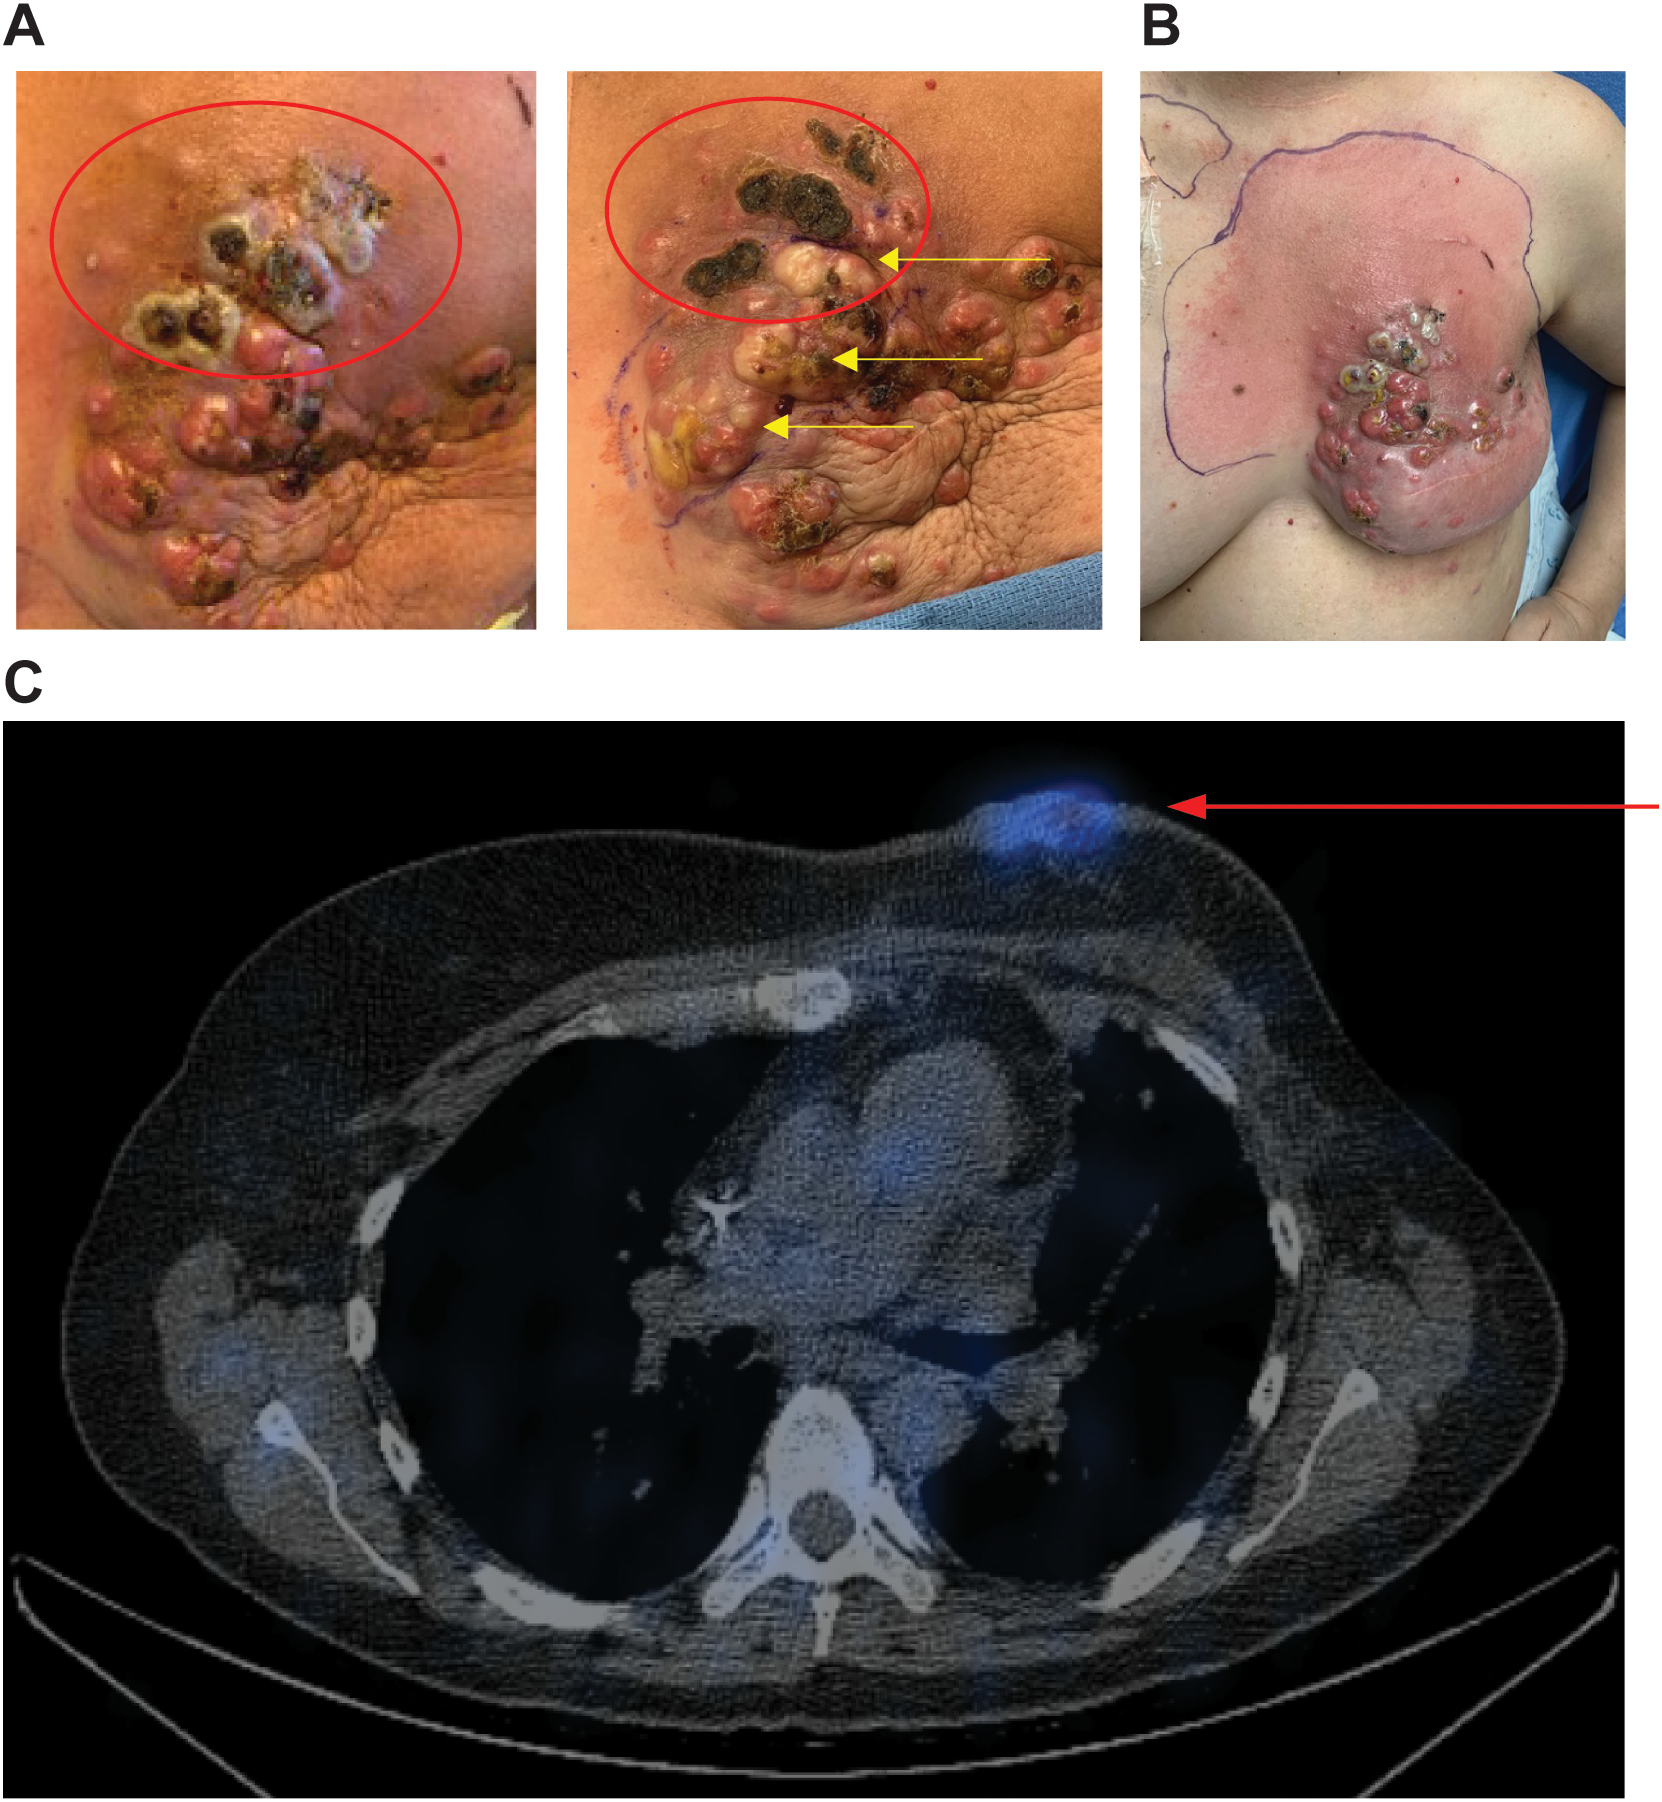

SPECT images for the second patient are shown in Figure 4C. This patient initially presented in 2014 at age 39 with de novo stage IV ER+, HER2- breast cancer with metastasis to the left axillary lymph nodes and left rib. She was initially started on ovarian suppression, denosumab, and endocrine therapy, which controlled her disease well until June 2020, when she had disease progression at the breast. She then started fulvestrant and cyclin-dependent kinase (CDK) 4/6 inhibitors but did not tolerate multiple CDK 4/6 inhibitors and subsequently had disease progression. She then started albumin-bound paclitaxel, followed by eribulin, with continued disease progression. PET/CT scans in December 2020 showed no evidence of distant metastasis, but there was continued progression at the breast, and she underwent mastectomy with sentinel lymph node biopsy with pathology showing grade 3 invasive lobular carcinoma 13.5 cm in size with dermal invasion, margins positive, 3/3 positive lymph nodes, and biomarkers now triple negative. She subsequently underwent radiation to the left chest wall and nodal basins. Four months after radiation, she developed new left chest wall dermal nodules, which were biopsied and consistent with TNBC. Staging scans showed new hepatic metastases and bony metastases. She was started on carboplatin and gemcitabine, complicated by profound cytopenias. She was switched to sacituzumab govitecan with disease progression. She was then switched to adriamycin and cyclophosphamide with progression, followed by fam-trastuzumab deruxtecan-nxki with continued progression. She was subsequently enrolled in the CF33-hNIS-antiPDL1 clinical trial at dose level three (1x106). She had a robust clinical response to her first injection, with pain and erythema throughout the left chest wall. On clinical exam, she had necrosis of the injected lesions (Figures 4A, B). She was admitted to the hospital, started on empiric antibiotics, and underwent extensive testing, which ruled out infectious causes. The leading cause for her erythema and pain in the left chest wall was a robust injection site reaction. The reaction subsequently resolved without further treatment. Her second dose of OV was delayed by one week to allow for recovery and was dose reduced per protocol (3x105). She tolerated the second dose well, but her disease progressed at the non-injected sites of the chest wall and sites of distant metastasis, and she came off-trial. SPECT imaging scans at C1D8 showed enhancement at the injected left chest wall dermal nodules (Figure 4C).

Figure 4

Robust injection site reaction and uptake on SPECT imaging following treatment with dose level 3. (A) Patient 2 received CF33-hNIS-antiPDL1 at dose level 3 (1x106 PFU). Injected lesions were superior left chest wall nodules. Injected nodules demonstrated necrosis on clinical exam (red ovals). The image on the left shows C1D11, right shows C1D21 with continued necrosis of superior injected lesions and blanching of lesions inferior to that following injection #2 into the inferior lesions (yellow arrows). (B) Robust injection site reaction shown on C1D8 with surrounding erythema. (C) SPECT imaging showed enhancement of injected nodules (red arrow).